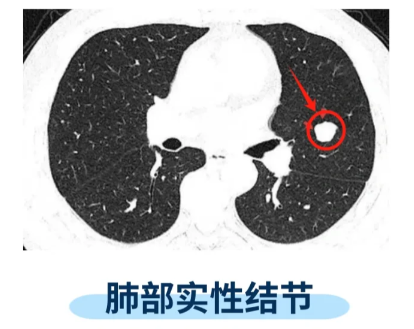

3mm肺部结节是否有意义不能一概而论,需结合以下因素综合判断结节形态若3mm结节边缘不规则存在分叶毛刺或胸膜牵拉征等特征,提示恶性可能性较高这类形态学异常通常与肿瘤细胞的侵袭性生长相关,需引起重视结节位置位于肺上叶或靠近胸膜的结节,恶性风险相对增加尽管3mm结节直径较小,但若。

3mm肺部结节的危险性需综合评估,总体恶性概率较低,但需结合具体情况判断从结节大小来看,3mm的肺部结节属于微小结节范畴一般来说,结节越大,恶性可能性越高,而3mm的结节因体积较小,其恶性概率相对较低但大小并非唯一判断标准,需结合其他特征综合分析结节形态是关键指标良性结节通常表现为边缘。

一3mm肺部小结节的普遍性质直径3mm的肺部小结节属于微小结节范畴,恶性概率较低此类结节多无明显症状,常在体检或因其他疾病检查时偶然发现其形成原因多样,包括肺部感染肺结核肺良性肿瘤或肺癌早期病变等,但体积越小,恶性风险越低二常规处理原则对于无高危因素的普通人群,3mm结节通常无需。

肺结节3mm多数情况下不严重,但仍需结合个体情况综合判断1 3mm肺结节的性质与风险3mm的肺结节属于微小肺结节,在临床中较为常见,绝大多数为良性病变其形成原因可能与肺部微小炎症吸收后的修复痕迹有关,例如既往轻微肺部感染如肺炎支气管炎愈合后,局部组织增生形成结节也可能是肺内正常淋巴。

若结节为良性,通常不严重3mm的肺部结节属于微小结节范畴,其良性原因多与长期吸烟肺部感染或炎症修复过程中形成的瘢痕有关此类结节对肺功能影响较小,患者多无明显症状,临床风险较低,无需特殊治疗,但需定期随访观察若结节为恶性,则需高度重视尽管3mm结节为肺癌的概率较低,但恶性结节可能存在。